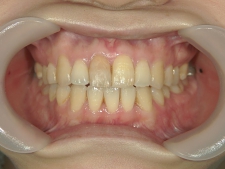

矯正歯科 治療前矯正歯科 治療前

矯正_灰色.pngno.37_7548_治療前_上.JPG矯正_灰色.png

no.37_7548_治療前_右.JPGno.37_7548_治療前_正面.JPGno.37_7548_治療前_左.JPG